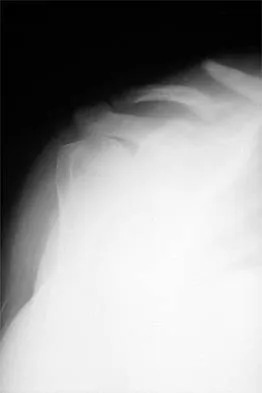

A 40-year-old woman who is an avid tennis player reports the insidious onset of progressive left shoulder pain for the past 2 months. Examination reveals full range of motion with a positive impingement sign. Strength in the supraspinatus and infraspinatus muscles is normal, although stress testing is painful. An earlier subacromial cortisone injection provided good, but only temporary relief. An AP radiograph of the left shoulder is shown in Figure 10. Management should now consist of